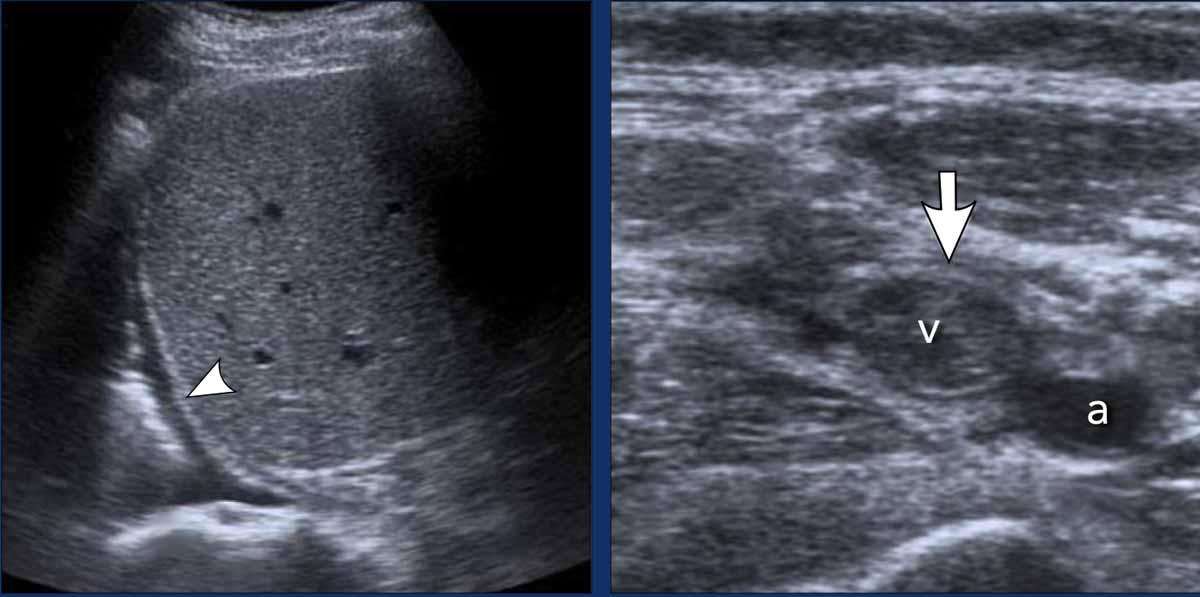

Bệnh nhân nam 52 tuổi nhập viện với chẩn đoán viêm màng ngoài tim cấp do nhiễm trùng và đau thượng vị cấp.

- Siêu âm cạnh ức trái cho thấy tràn dịch màng ngoài tim kèm dày màng ngoài tim (đầu mũi tên). Không phát hiện bất thường ở ổ bụng.

- CT có thuốc cản quang xác nhận sự hiện diện của tràn dịch màng ngoài tim được bao quanh bởi màng ngoài tim dày và ngấm thuốc (mũi tên).

Dẫn lưu màng ngoài tim thu được dịch tiết viêm, nhiều khả năng có nguồn gốc virus. Sau khi điều trị viêm màng ngoài tim, các triệu chứng ở bụng của bệnh nhân dần dần thuyên giảm.

Bệnh nhân nam 49 tuổi bị chèn ép tim, biểu hiện chủ yếu bằng đau bụng trên.

- Siêu âm túi mật theo mặt cắt dọc cho thấy thành túi mật dày lan tỏa (đầu mũi tên). Mặc dù hình ảnh này có thể gợi ý viêm túi mật, nhưng sự vắng mặt của sỏi túi mật và tình trạng căng giãn túi mật gợi ý nguyên nhân ngoại sinh.

- Siêu âm gan theo mặt cắt ngang cho thấy tĩnh mạch chủ dưới (IVC) giãn và các tĩnh mạch gan giãn to (đầu mũi tên), phù hợp với suy tim phải.

- Siêu âm cạnh ức trái xác định tràn dịch màng ngoài tim lượng nhiều (mũi tên), phù hợp với viêm màng ngoài tim cấp vô căn là nguyên nhân nền.